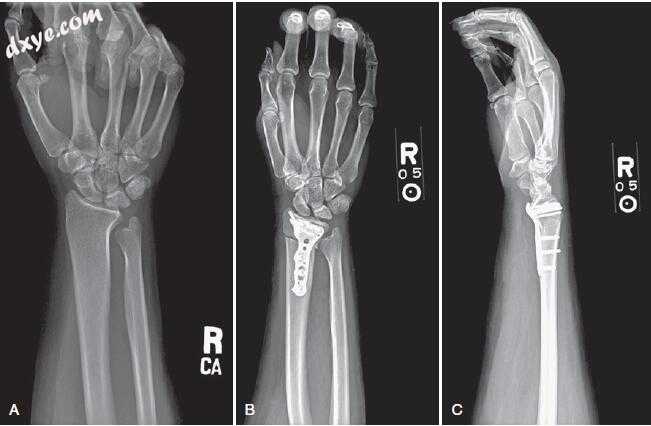

59.jpg

图.59  A,桡骨短缩截骨术后的X线片。 将前臂缩短截骨板(AcuMed,Hillsboro,OR)置于桡骨掌侧表面。 现在患者是尺骨中间的。 B,侧位X光片显示沿径向缩短截骨后桡骨掌侧方向的解剖轮廓钢板。